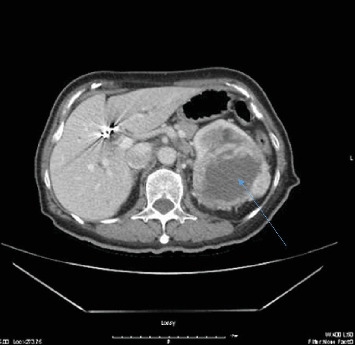

Abstract Image

Immune checkpoint inhibitors have revolutionized cancer treatment, yet their use is associated with unique and sometimes unpredictable immune-related adverse events. We present a case of a 67-year-old female with renal cell cancer treated with ipilimumab and nivolumab who developed aseptic meningitis and hypophysitis. This case highlights the challenges in managing immune-related adverse events and underscores the need for vigilance in monitoring patients receiving ICIs.